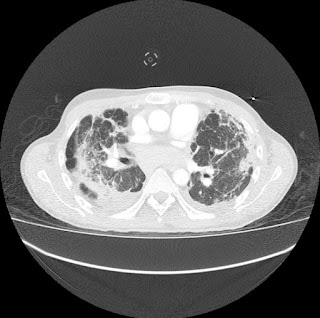

Escanografía